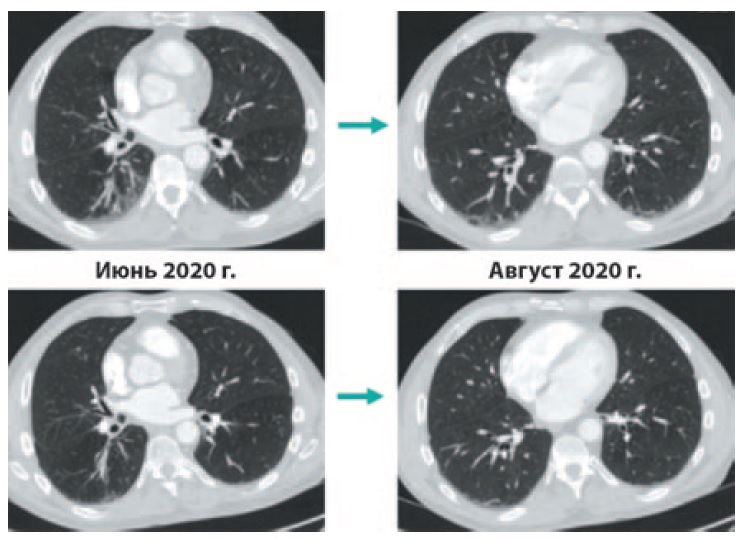

В июне 2020 г. при контрольной компьютерной томографии – КТ (рис. 5) у пациента выявлена правосторонняя нижнедолевая пневмония. Клинические проявления пневмонии отсутствовали, также не было выявлено отклонений лабораторных показателей. По результатам тестирования методом полимеразной цепной реакции РНК возбудителя COVID-19 не обнаружена. Также не выявлено антител классов IgM и IgG к возбудителю COVID-19. По согласованию с мультидисциплинарной комиссией решено продолжить иммунотерапию в прежнем режиме. По данным КТ грудной клетки от августа 2020 г. (см. рис. 5) отмечен регресс правосторонней нижнедолевой бронхопневмонии.

Рис. 5. КТ грудной клетки: регресс правосторонней нижнедолевой бронхопневмонии. / Fig. 5. Computed tomography of the chest: the regression of right-sided lower lobe bronchopneumonia.

В настоящий момент пациент продолжает поддерживающую терапию дурвалумабом, отмечается полный регресс заболевания. Ответ на терапию в динамике представлен на рис. 6. Всего с июня 2017 по март 2021 г. пациент получил 50 введений дурвалумаба. Таким образом, пациент получает терапию на протяжении 45 мес с сохранением полного регресса опухоли и без НЯ, связанных с лечением.